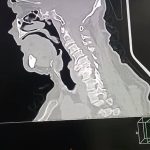

حيث استقبل المستشفى مريضًا يبلغ من العمر 70 عامًا، كان يعاني من ضعف تام وشلل كامل بالأطراف الأربعة، مع فقدان شبه كامل للتحكم في البول والبراز، وذلك على خلفية ادعاء التعرض للسقوط. وبإجراء الفحوصات الطبية والأشعات اللازمة، تبين إصابة المريض بانزلاق غضروفي عنقي متعدد على أربعة مستويات،

ما أدى إلى حدوث كدمة بالحبل الشوكي وضيق كامل بالقناة الشوكية العنقية، وهي من الحالات شديدة الخطورة التي تستدعي تدخلاً جراحيًا دقيقًا وعاجلًا.

وعلى الفور تم تجهيز الحالة طبيًا من خلال إجراء جميع الفحوصات والتحاليل اللازمة، قبل أن يخضع المريض لجراحة ميكروسكوبية دقيقة ومعقدة، تم خلالها استئصال الغضاريف المنزلقـة، وتركيب أقفاص عنقية مثبتة بدعامات ذاتية (Stand-alone) على أربعة مستويات، وذلك باحترافية عالية، مع خروج المريض من غرفة العمليات في حالة مستقرة وآمنة.